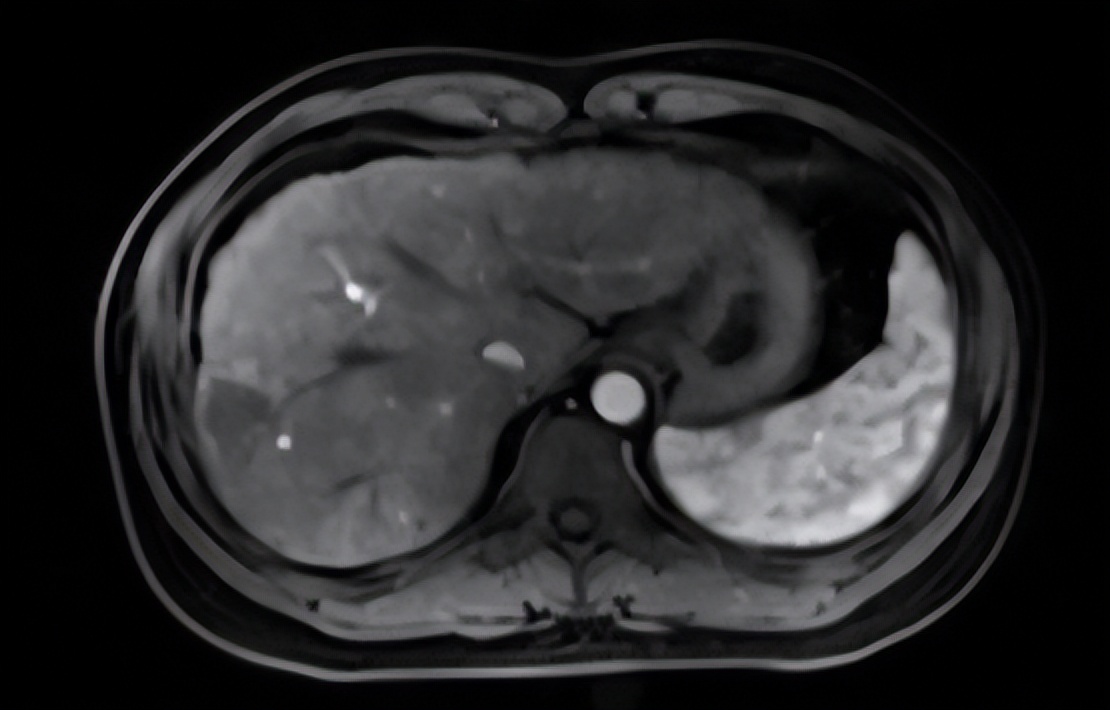

患者男性35岁,既往“慢性乙型肝炎”病史多年;1月前无明显诱因出现肝区不适,伴隐痛,饮食正常,查甲胎蛋白31.50ng/ml,进一步查上腹部MRI示提示肝右后叶病变,大小约2.0cm×1.2cm、考虑HCC;超声造影进一步提示原发性小肝癌。

术前增强磁共振考虑肝细胞肝癌